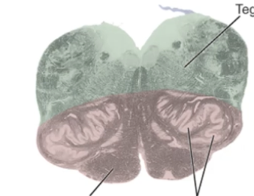

A

midbrain

pons